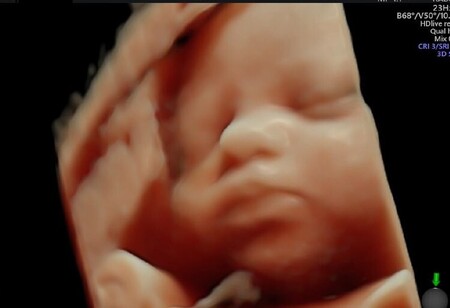

Puede hacer gestos

Ecografia

De vez en cuando salen a la luz ecografías en las que vemos a los bebés haciendo distintos tipos de gestos (a mi se me quedó grabado en la mente aquél bebé que mostró una señal de "ok" en su ecografía), como articular, sacar la lengua, bostezar, succionar, parpadear, fruncir el ceño, y sonreír. Las investigaciones muestran que los empiezan a hacer a partir del cuarto mes de embarazo, pero que su evolución es bastante rápida, así que la frecuencia de esos gestos del feto es indicadora de su correcto desarrollo neurológico.